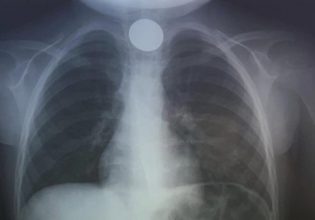

Πριν από μερικές μέρες, 28χρονη γυναίκα πραγματοποίησε εγχείρηση γυναικολογικής φύσεως στο νοσοκομείο της Κω, την Τετάρτη 21 Φεβρουαρίου. Μετά από το χειρουργείο ένιωθε πολύ δυνατούς πόνους, με αποτέλεσμα να μεταβεί σε ιδιώτη γυναικολόγο για να εξεταστεί.

Κατά την διάρκεια της εξέτασης που έγινε στις 27 Φεβρουαρίου, μία περίπου εβδομάδα μετά την εγχείρηση, διαπιστώθηκε ότι στο σώμα της γυναίκας είχαν ξεχαστεί πολλές γάζες. Η κοπέλα στη συνέχεια μετέβη στο νοσοκομείο της Κω όπου μετά από νέα επέμβαση της αφαιρέθηκαν οι γάζες.